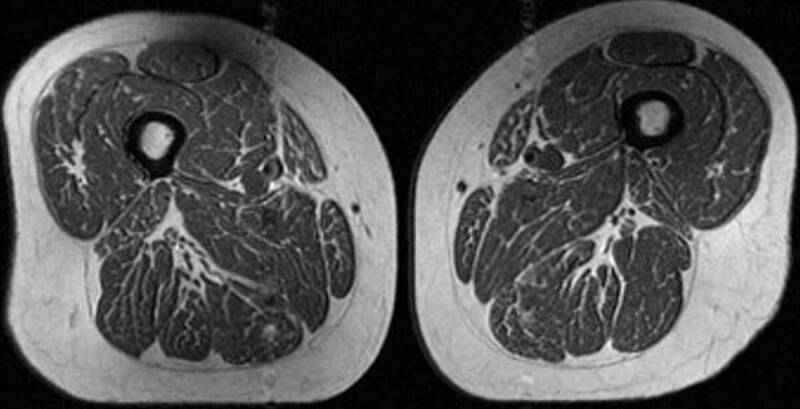

〔編譯陳成良/綜合報導〕你每天吃的東西,可能正在悄悄改變你的肌肉。不少人以為體重沒明顯上升就沒問題,但最新影像研究發現,即使外表看起來正常,肌肉內部也可能出現類似「牛排油花」的脂肪滲入現象。

根據美國有線電視新聞網(CNN)報導,研究刊登於《放射學》(Radiology)期刊,由舊金山加州大學團隊分析615名受試者的核磁共振(MRI)影像,並比對飲食習慣。結果顯示,攝取越多超加工食品的人,其大腿肌肉內的脂肪含量越高,兩者呈現明顯關聯。

這種變化並不是一般理解的「變胖」。研究人員指出,脂肪並非只堆積在皮下,而是滲入肌肉纖維之間,讓原本應該緊實的肌肉,看起來像高級牛排上的油花紋路。換句話說,就算體重沒有明顯增加,肌肉品質仍可能已經開始下降。

研究同時發現,這種肌肉脂肪增加的現象,與總熱量攝取沒有直接關係,而是與「超加工食品比例」更為相關。